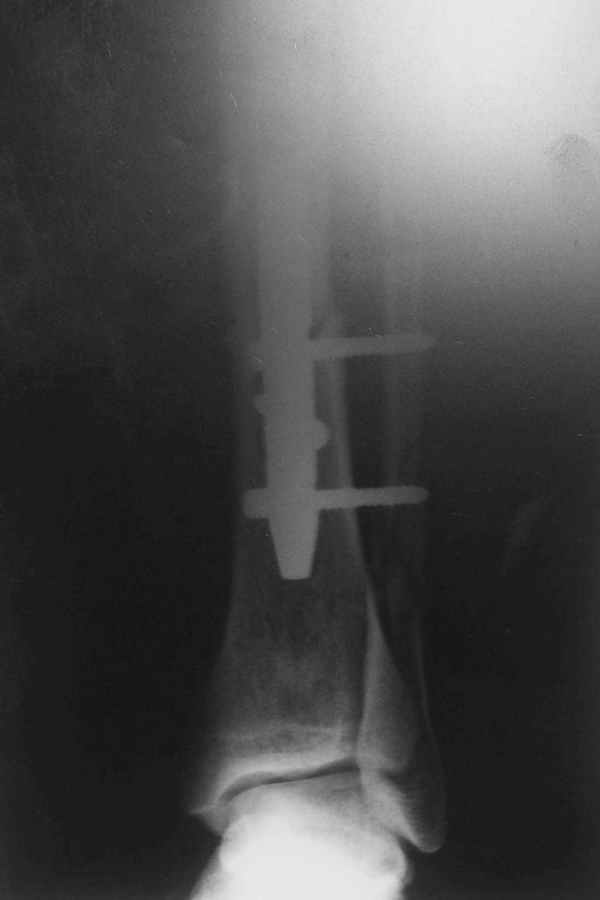

В 2002 г. была у нас больная с ложным суставом бедра и остеомиелитом (как оказалось), после удаления пластины. Гвоздь с блокированием.

Потекло через месяц - открылось 2 свища по старому рубцу от давно удаленной пластины. На фоне гноя раза три завинчивал обратно винты, которые вылезали латерально, прямо через свищ. Потом таки провел дополнительно винты мимо гвоздя, и убрал вверху статический винт. Острый гнойный процесс стих, свищи мыла она дома дважды в день водным хлоргексидином, ходила с возрастающей нагрузкой, а к 10 мес. и свищи закрылись, и срослось. Итоговые снимки от 18 апреля 2003 г. прилагаю.

Рентгенограмы

Не удается отправить первичные снимки. А что скажите по имеющимся?!

Отправитель: А. Миронов 21 Январь 2005, 20:49

Уважаемый Валентин!

Выполненный остосинтез нестабилен. Штифт надо заменить по "размеру" на солидный, дистльно три запирающих винта. Успехов!

Отправитель: Alexander Chelnokov 21 Январь 2005, 21:31

Перелом спиральный, то есть низкоэнергетический, так что со сращением дело обстоит уже неплохо, лишь бы "костоеда" не развилась. Отломки выглядят уже стабилизированными костной мозолью, так что довводить винты, наверно, уже незачем. Разве что при клинической оценке подвижность еще есть - тогда можно для стабилизации наложить простейший аппарат, не опасаясь контакта его элементов с гвоздем, поскольку места в дистальном метафизе оставлено более чем достаточно.

Отправитель: Djoldas Kuldjanov, M.D. 21 Январь 2005, 23:48

С Александром согласен, нет необходимости делать дополнительные усилия для сращения, не большая компрессия аппаратом из двух колец и полная нагрузка доделает работу.